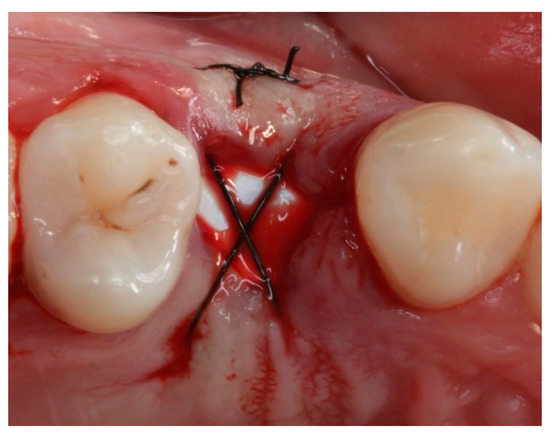

Socket Preservation Using a (Dense) PTFE Barrier with or without Xenograft Material: A Randomized Clinical Trial

2. Materials and Methods

2.4. Groups